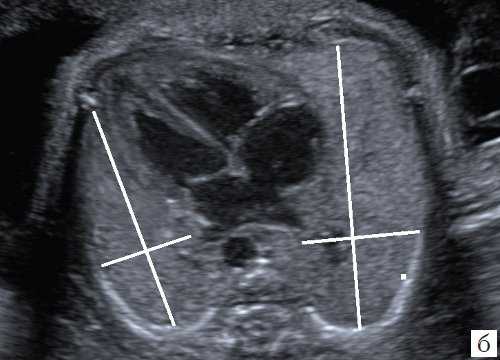

При сравнении изображения в 2D режиме, по которому производились первоначальные измерения, и ультразвукового среза, полученного ретроспективно из сохраненного объема видны ошибки, допущенные при измерениях (рис. 4), и прежде всего отсутствие четкой картины четырехкамерного среза сердца и небольшое увеличение снимка. На этом этапе работы использование новых технологий позволило нам более объективно оценить ранее полученные данные.

а) Нарушены правила оценки: нет четкого изображения четырехкамерного среза сердца.